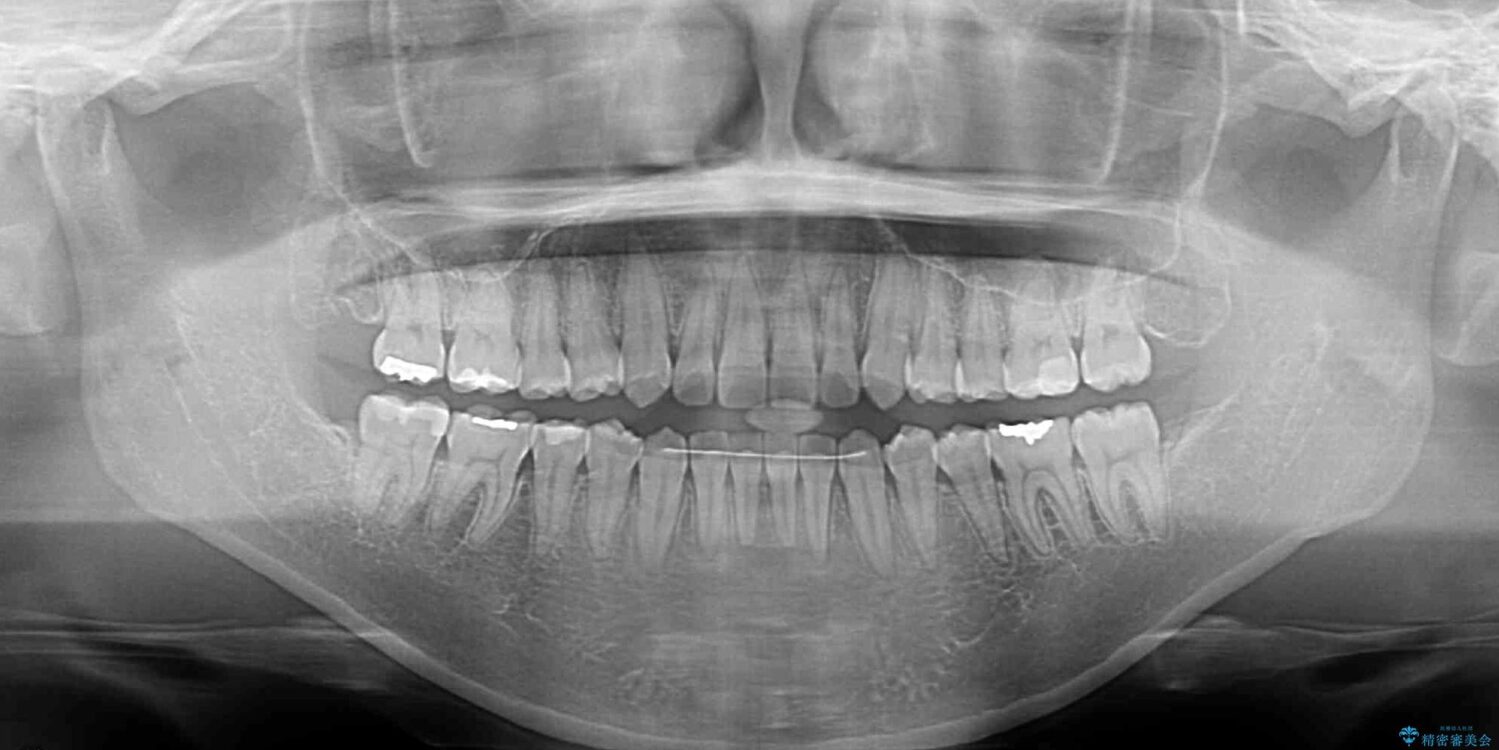

前歯の叢生と八重歯を気にして来院された患者様です。

治療前

• 【モニター】カリエール・ディスタライザーを併用した八重歯のインビザライン矯正 治療前画像